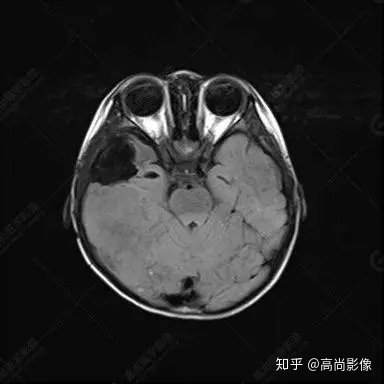

右側(cè)顳葉腫瘤切除術(shù)后(具體不詳):右側(cè)顳部骨質(zhì)不連續(xù)呈術(shù)后改變,右側(cè)顳葉術(shù)區(qū)見片狀長T1長T2信號影,F(xiàn)LAIR呈低信號;術(shù)區(qū)后方右側(cè)顳枕葉見一巨大占位性病變影,邊界欠清,大小約6.2×5.8×4.3cm(前后×左右×上下),信號不均勻,T1WI呈等稍低信號間雜少許高信號,T2WI呈高稍低混雜信號,DWI示部分病灶彌散受限,相應(yīng)ADC圖減低,磁敏感序列見部分呈極低信號,增強(qiáng)掃描可見明顯不均勻強(qiáng)化,鄰近硬腦膜及小腦幕增厚并明顯強(qiáng)化;另延髓右前方及右側(cè)橋小腦角區(qū)見一不規(guī)則形異常信號影,大小約3.2×1.3×3.7cm(左右×前后×上下),呈長T1稍長T2信號,F(xiàn)LAIR呈等信號,DWI未見受限,增強(qiáng)后明顯均勻強(qiáng)化,鄰近腦膜明顯強(qiáng)化。鄰近腦實質(zhì)及右側(cè)顳角明顯受壓;左側(cè)大腦半球未見局灶性信號異常,中線結(jié)構(gòu)稍左移。

右側(cè)顳葉腫瘤切除術(shù)后:現(xiàn)術(shù)區(qū)后方右側(cè)顳枕葉及延髓右前方占位,右側(cè)顳枕部硬腦膜及小腦幕明顯強(qiáng)化,結(jié)合既往影像資料,考慮為胚胎源性惡性腫瘤,如非典型畸胎樣/橫紋肌樣瘤(AT/RT)或原始神經(jīng)外胚層腫瘤(PNET)。

非典型畸胎樣/橫紋肌樣瘤(AT/RT) 是一種高度惡性中樞神經(jīng)系統(tǒng)腫瘤,臨床罕見,臨床表現(xiàn)無特異性,好發(fā)于 5 歲以下兒童,尤以 3 歲以下多見,在兒童原發(fā)性中樞神經(jīng)系統(tǒng)(CNS)腫瘤中占 1%~3%。該腫瘤體積一般較大,幕上大于幕下,有明顯的占位效應(yīng)。該腫瘤成分復(fù)雜,囊變、出血、壞死常見。因此 AT/RT信號混雜,囊性部分呈 T1WI低、T2WI高信號,增強(qiáng)后不強(qiáng)化;若瘤體出血,囊內(nèi)可見T1WI稍高信號、T2WI低信號,實性部分在 T1WI上呈混雜等、低信號,在T2WI 及 T2-FLAIR上呈混雜等高信號,增強(qiáng)掃描后大部分呈環(huán)形條帶樣明顯強(qiáng)化,中心壞死區(qū)不強(qiáng)化。另外,該腫瘤實性成分在DWI上呈高信號,說明腫瘤細(xì)胞核密集,水分子擴(kuò)散明顯受限,提示該腫瘤惡性程度高,容易復(fù)發(fā)及轉(zhuǎn)移。